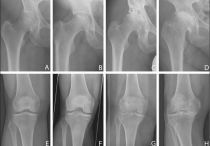

Боль внутри сустава может быть разной: сильной, слабой, ноющей или жгучей, но всегда она доставляет массу дискомфорта. Болевой синдром не дает человеку нормально двигаться, заниматься спортом, работать и даже отдыхать. Мучительные ощущения пронизывают сочленения насквозь.

Боли в суставах могут быть спровоцированы разными причинами: нарушением обменных процессов в организме и сочленении; неправильном кровообращении внутри мягких тканей, что не позволяет нормально питать хрящ. Кроме того, появлению боли способствуют инфекционные, системные, воспалительные, ревматические, эндокринные заболевания. Вызываются неприятные ощущения тем, что раздражитель активно воздействует на нервные окончания, которые тянутся от синовиальной сумки.

Какой бы ни была причина появления дискомфорта в суставе, повседневная жизнь больного значительно ухудшается. Часто человек может даже потерять свою трудоспособность и стать инвалидом.

Чтобы этого не допустить, необходимо обязательно лечиться. Но самостоятельно это делать не следует. Консультация грамотного специалиста – залог эффективности терапии. Если болят суставы, то это может говорить о развитии серьезной патологии в организме. Шутить с таким состоянием нельзя.